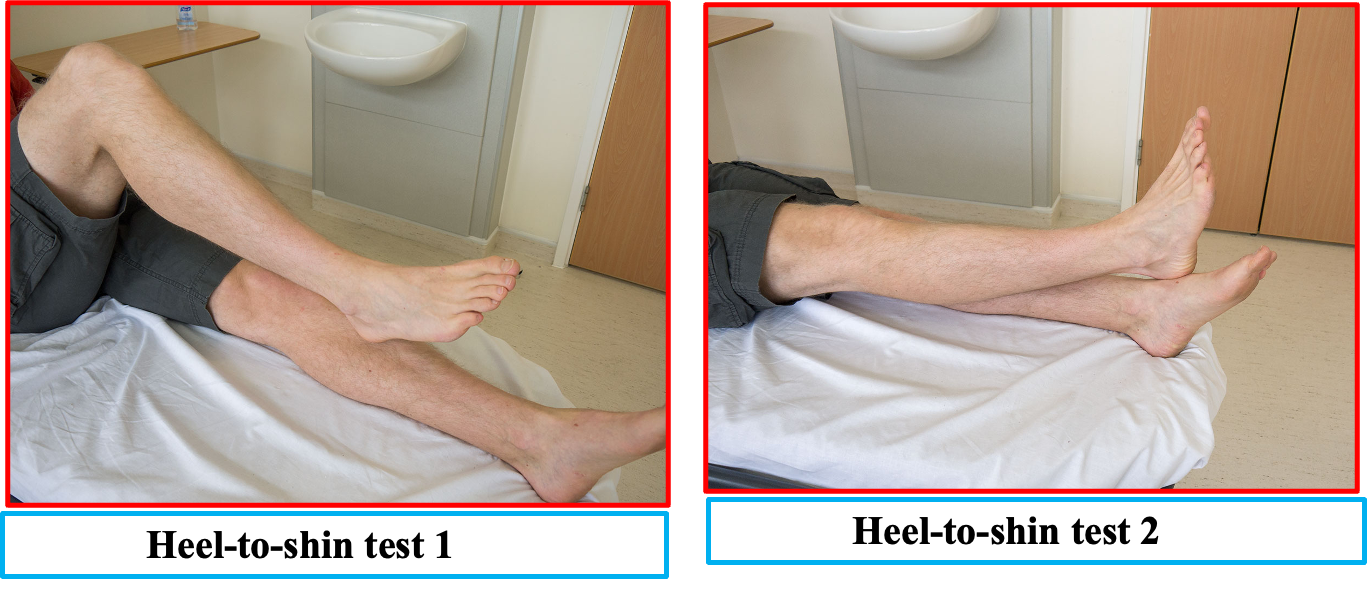

D) Heel-to-Knee Test

HEEL SHIN TEST

Perform the heel-to-shin test. Have the patient lying down for this and get them to run the heel of one foot down the shin of the other leg, and then to bring the heel back up to the knee and start again. Repeat the test with the other leg.